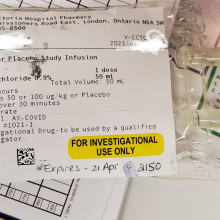

Clinical trials begin to treat COVID-19 patients with sepsis

It’s a discovery that has been more than ten years in the making: the use of a human protein to potentially treat patients with sepsis. Lawson Scientist Dr. Qingping Feng noticed that a human protein called annexin A5 showed positive results with sepsis back in 2007. Fast forward 14 years later to now, and this discovery could very well be the first ever viable treatment for sepsis patients, including severe COVID-19 patients who develop sepsis. Read more.